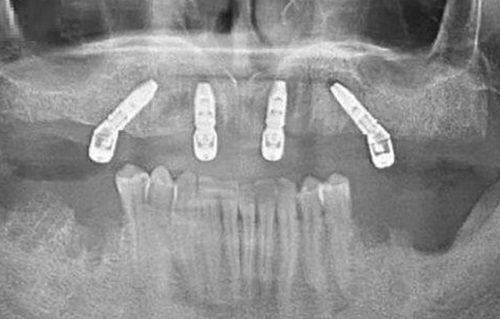

再如北京佳美口腔门诊部的佳美即刻种植牙,术中通过数字化影像扫描定位,种植牙定位精细、操作快捷省时、成功几率高。北京中腾口腔医院在种植牙技术上也与国内外接轨,相信在收费合理的情况下,能为患者提供不逊色于其他医院的服务。